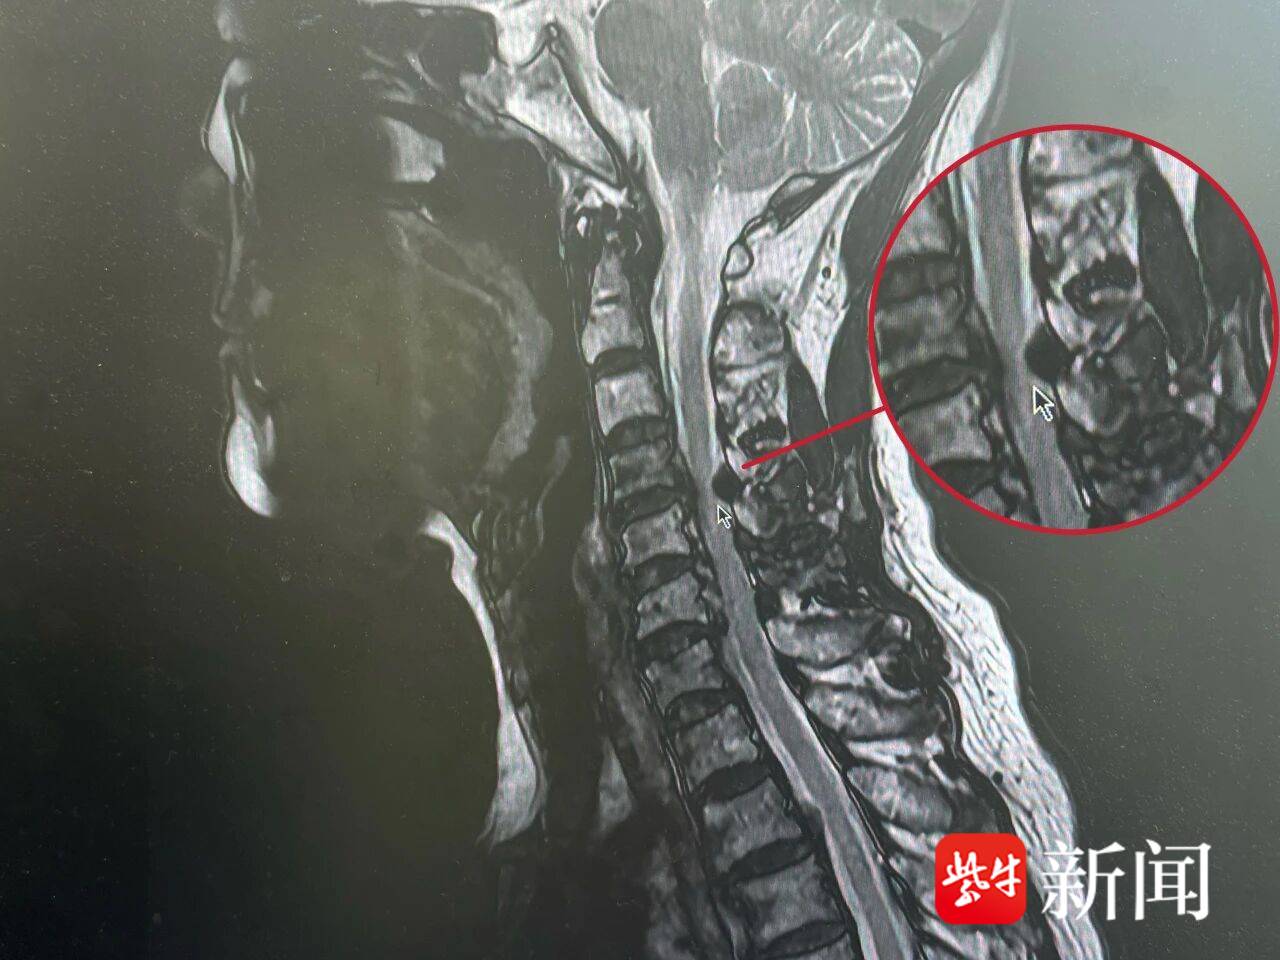

患者磁共振影像。通讯员供图

经过查体和相关影像学检查,发现患者颈椎4/5脊髓受压严重,初步考虑其黄韧带骨化导致椎管狭窄。“你看这里,脊髓已经遭到严重压迫,不仅影响生活质量,还可能面临瘫痪。”张兴指着屏幕上的影像介绍说,“唯一解决办法就是通过手术取出压迫脊髓的肿物。”